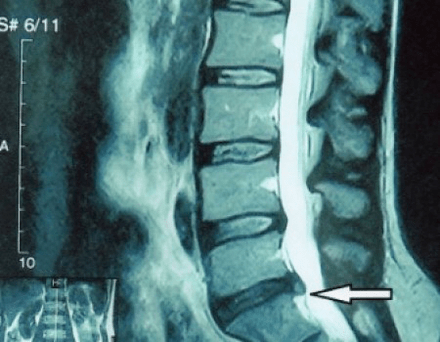

An “X-ray” of the cervical spine, and even with functional tests for flexion and extension, does not show cartilage, since their tissue transmits X-rays.Despite this, based on the location of the vertebrae, one can draw general conclusions about the height of the intervertebral discs, the general straightening of the physiological curvature of the neck - lordosis, as well as the presence of marginal growths on the vertebrae with prolonged irritation of their surfaces by fragile and dehydrated intervertebral discs.Functional tests can confirm the diagnosis of instability in the cervical spine.

Since the discs themselves can only be seen using CT or MRI, magnetic resonance and x-ray computed tomography are indicated to clarify the internal structure of cartilage and formations such as protrusions and hernias.Thus, with the help of these methods, a diagnosis is accurately made, and the tomography result is an indication, and even a topical guide, for the surgical treatment of a hernia in the neurosurgery department.

- if you have a hernia, then you need to dynamically monitor it, do regular MRIs, avoid increasing its size, or carry out modern minimally invasive surgical treatment, since without exception, all conservative methods of treating exacerbation of osteochondrosis leave the hernia in place, and only eliminate temporary symptoms: inflammation, pain, shooting and muscle spasms.

- You can regularly do at least an x-ray of the lumbar spine in two projections, or an MRI, to know whether the hernia, if any, is progressing;